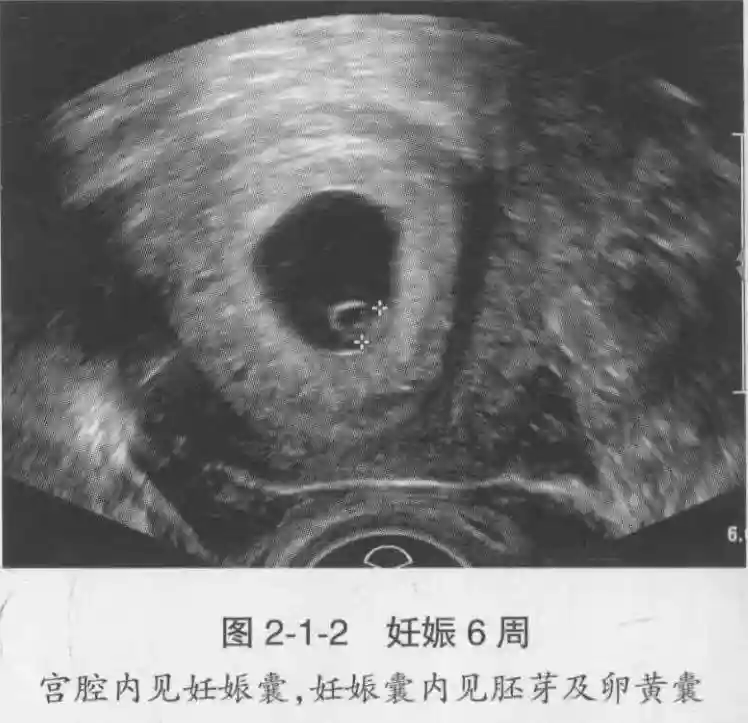

2??卵黄囊:是妊娠囊内第一个解剖结构,直径<7mm。表现为小环状,中央为无回声,囊壁薄,内透声好。卵黄囊位于胚胎旁胚外体腔内。卵黄囊通常在孕5-6周时出现,5-10周稳步增长,一般不超过7mm,至12周消失。妊娠囊的大小与卵黄囊之间有一定关系,妊娠囊平均直径> 8 mm 时,经阴道超声均应显示卵黄囊,妊娠囊平均直径> 18 mm 时,经腹超声均应显示卵黄囊。

3??胚胎:胚胎通常在6-7周时可以为超声显示,起初为胎芽,表现为卵黄囊一侧局部组织增厚,达到1 -2 mm 时才有可能为超声测量出来。达4-5mm时可见胎心搏动,相应孕周为6-6.5周,妊娠囊大小为13-18mm。胚芽长度≥7㎜时仍未见心管搏动,提示胚胎停止发育。胚胎的出现和妊娠囊直径的关系:妊娠囊直径> 16 mm 时,经阴道超声应显示胚胎。妊娠囊直径> 25 mm 时,经腹超声均应显示胚胎。